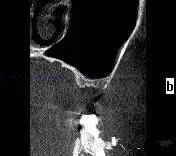

第三圖:上頜竇氣化導(dǎo)致上頜竇過大,上頜竇底骨質(zhì)向紙張一樣薄。只適合做外提升。